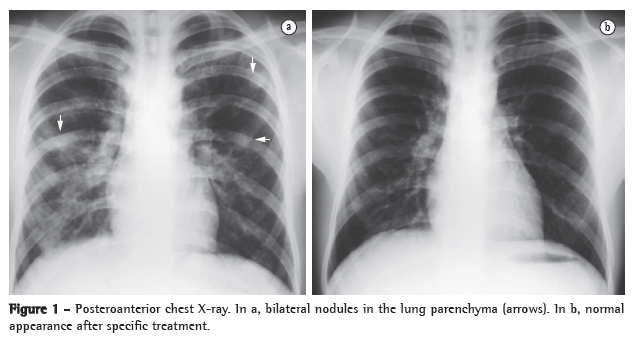

We report the case of a 16-year-old male patient who reported that, one week after having swum in a pond, he had experienced fever and epigastric pain followed by diarrhea, vomiting, and joint pain. The patient also reported that, five days before seeking medical attention, he had experienced transitory facial exanthema and dry cough. The time elapsed between the onset of the symptoms and the first medical appointment was 20 days. The results of the laboratory tests performed during his hospital stay were as follows: leukocyte count of 16,500-26,700 cells/mm3, the proportion of eosinophils ranging from 23% to 66%; and positive parasitological stool examination (PSE) results for S. mansoni eggs. Posteroanterior chest X-rays revealed various nodular opacities that had ill-defined borders and were diffusely distributed throughout the lungs. The opacities disappeared after specific treatment (Figures 1a and 1b). An HRCT scan of the chest showed the pulmonary lesions in greater detail and revealed various nodules that were diffusely distributed throughout the lung parenchyma, predominantly in the cortical regions, and measured, on average, 10.0 mm; most of the nodules showed a weak halo surrounded by ground-glass attenuation (Figure 2). The patient was treated with three 1,050-mg doses of praziquantel. At the first outpatient follow-up visit, one month after discharge, the patient was asymptomatic, and the laboratory test results were as follows: leukocyte count of 7,850 cells/mm3 (eosinophils, 17%); and positive PSE results for S. mansoni eggs. At the second outpatient follow-up visit, two months after the treatment, the leukocyte count was 6,680 cells/mm3 (eosinophils, 9%), and the PSE results were negative for S. mansoni eggs.

Acute pulmonary schistosomiasis results from a hypersensitivity reaction that occurs within 16-90 days after cercariae have penetrated the skin and is due to the migration of eggs and schistosomula in the blood, initially to the lungs and subsequently to the hepatic portal system, where the eggs and schistosomula remain until their full maturation.(1,3,4) Although this phase is generally asymptomatic, variable clinical symptoms can occur, principally in nonimmune individuals; the symptoms include fever, headache, anorexia, vomiting, diarrhea, dry cough, arthralgia, and myalgia, as well as eosinophils, which can range from 10% to 75%.(1,3,4) The earliest pulmonary manifestations result from the migration of the parasite from the blood or lymph nodes to the lungs, creating a profile similar to that of Loeffler's syndrome. The radiographic pattern consists of bilateral and subpleural areas of pulmonary consolidation or ground-glass attenuation, which are typically transitory and migrate at short intervals; those areas typically disappear within one month.(4) In the acute phase of schistosomiasis, imaging tests generally reveal miliary micronodular infiltrate that spreads throughout both lungs and is similar to that seen in miliary tuberculosis or viral infection. Multiple, larger, nodules, secondary to granuloma formation, can also be seen,(4) sometimes surrounded by weak hypodensity of ground-glass appearance, designated the halo sign; this hypoattenuating halo that surrounds the nodules can be caused by immune complex deposition or eosinophilic infiltration.(1,6) The radiographic changes seen in such cases are nonspecific. However, when taken together with the clinical and laboratory findings, they allow the diagnosis of schistosomiasis. Early diagnosis and treatment of the disease are important in order to prevent severe late complications, such as pulmonary hypertension, cor pulmonale, and pulmonary arteriovenous fistulas.(4,6) It has been suggested that CT is the best imaging method for identifying pulmonary involvement in acute schistosomiasis, given that acute schistosomiasis can occur in the absence of respiratory symptoms.(1)